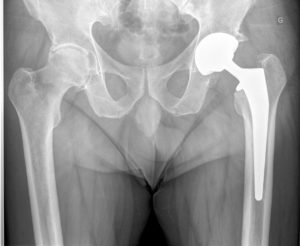

L'intervention de prothèse de hanche

Docteur Gaël Poirée